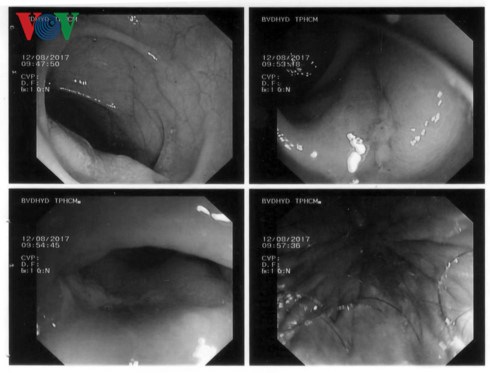

Tuy nhiên, vấn đề điều trị gặp nhiều thách thức như người bệnh lớn tuổi, có nhiều bệnh lý nội khoa nặng kèm theo, đặc biệt là người bệnh đang dùng thuốc kháng đông (nguy cơ chảy máu rất cao khi phẫu thuật hay làm thủ thuật) , nhờ ứng dụng phương pháp mới, kỹ thuật cắt niêm mạc (EMR – Endoscopic Mucosal Resection) qua nội soi đại tràng không cần phẫu thuật. Ba polyp lớn ở đại tràng chậu hông và trực tràng được cắt hoàn toàn, không tai biến chảy máu hay các tai biến khác , polyp ở trực tràng là polyp ung thư ở bề mặt (ung thư sớm) được cắt hoàn toàn qua nội soi, không cần phải phẫu thuật thêm. Sau khi điều trị polyp ung thư hóa ở trực tràng và đại tràng chậu hông, người bệnh được phẫu thuật cắt đại tràng phải để điều trị ung thư đại tràng ngang. Hiện tại, người bệnh đã bình phục và xuất viện.

| Vết cắt tại vị trí ung thư sớm và polyp lớn lành tốt. |